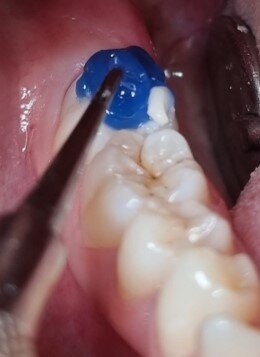

First, a thin layer of the resin was applied to the pits and fissures and polymerised (Fig. 2a). A medium-sized ball instrument was then placed on the occlusal surface already covered with the resin and a second layer of resin was added, enclosing the ball. The addition of layers was continued until both the surface and the instrument were sufficiently covered (Figs. 2b & c). The stamp was then separated from the tooth (Fig. 3).

Figs. 2a–c: The anatomy of the occlusal surface was copied with utility resin to create a stamp. The tip of a ball-shaped instrument was incorporated to give a handle to the stamp.

Fig. 3: The stamp shows a detailed imprint of the occlusal anatomy.